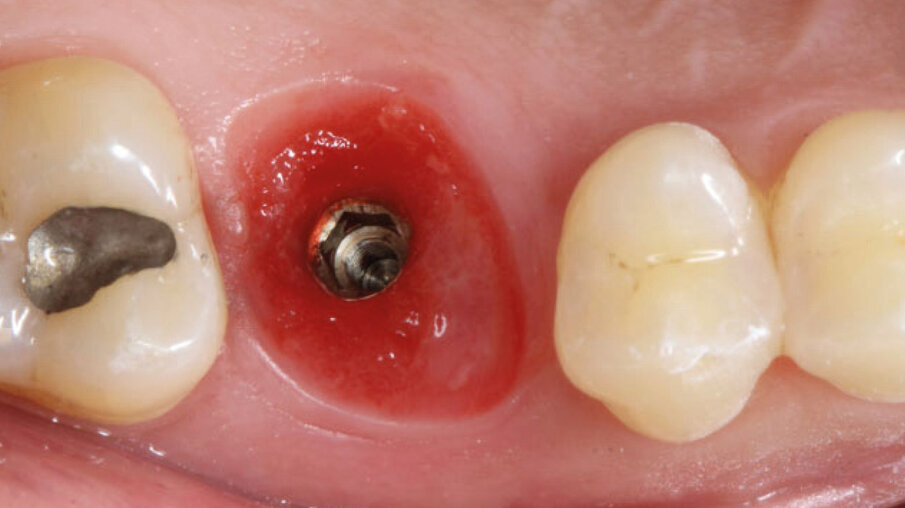

Dopo l’esecuzione dell’anestesia locale, il dente è stato rimosso e l’alveolo pulito dai residui del legamento parodontale. È stato inserito l’impianto (Zimmer TSV, Zimmer, Parsippany) 4.1 x 11,5 TSVM posizionato seguendo il protocollo consigliato dal produttore (Fig. 3). L’impianto è stato inserito a livello della cresta alveolare. È stato avvitato lo scan-abutment (Zfx Intrascan Matchholder, Zfx,). È stata rilevata un’impronta ottica intra-operatoria dell’emiarcata in cui è stato posizionato l’impianto con lo scan abutment (Fig. 3). Il gap tra l’osso vestibolare e l’impianto è stato riempito con Bio-Oss (Geistlich Pharma) (Fig. 4). Al termine della chirurgia è stato progettato e fresato il provvisorio, che è stato applicato appena pronto, dopo aver inserito la matrice in collagene volumetricamente stabile Fibro-Gide (Geistlich Pharma) precedentemente imbibita con il gel a base di polinucleotidi e acido ialuronico Regenfast (Officine Bio-Farmaceutiche Mastelli), al di sotto della vite stessa (Figg. 5, 6). Data l’accuratezza della vite non sono state necessarie suture. Al termine della procedura è stata eseguita una radiografia di controllo (Fig. 7).

Fig. 4_Inserimento implantare con zappatura del gap con Bio-Oss.